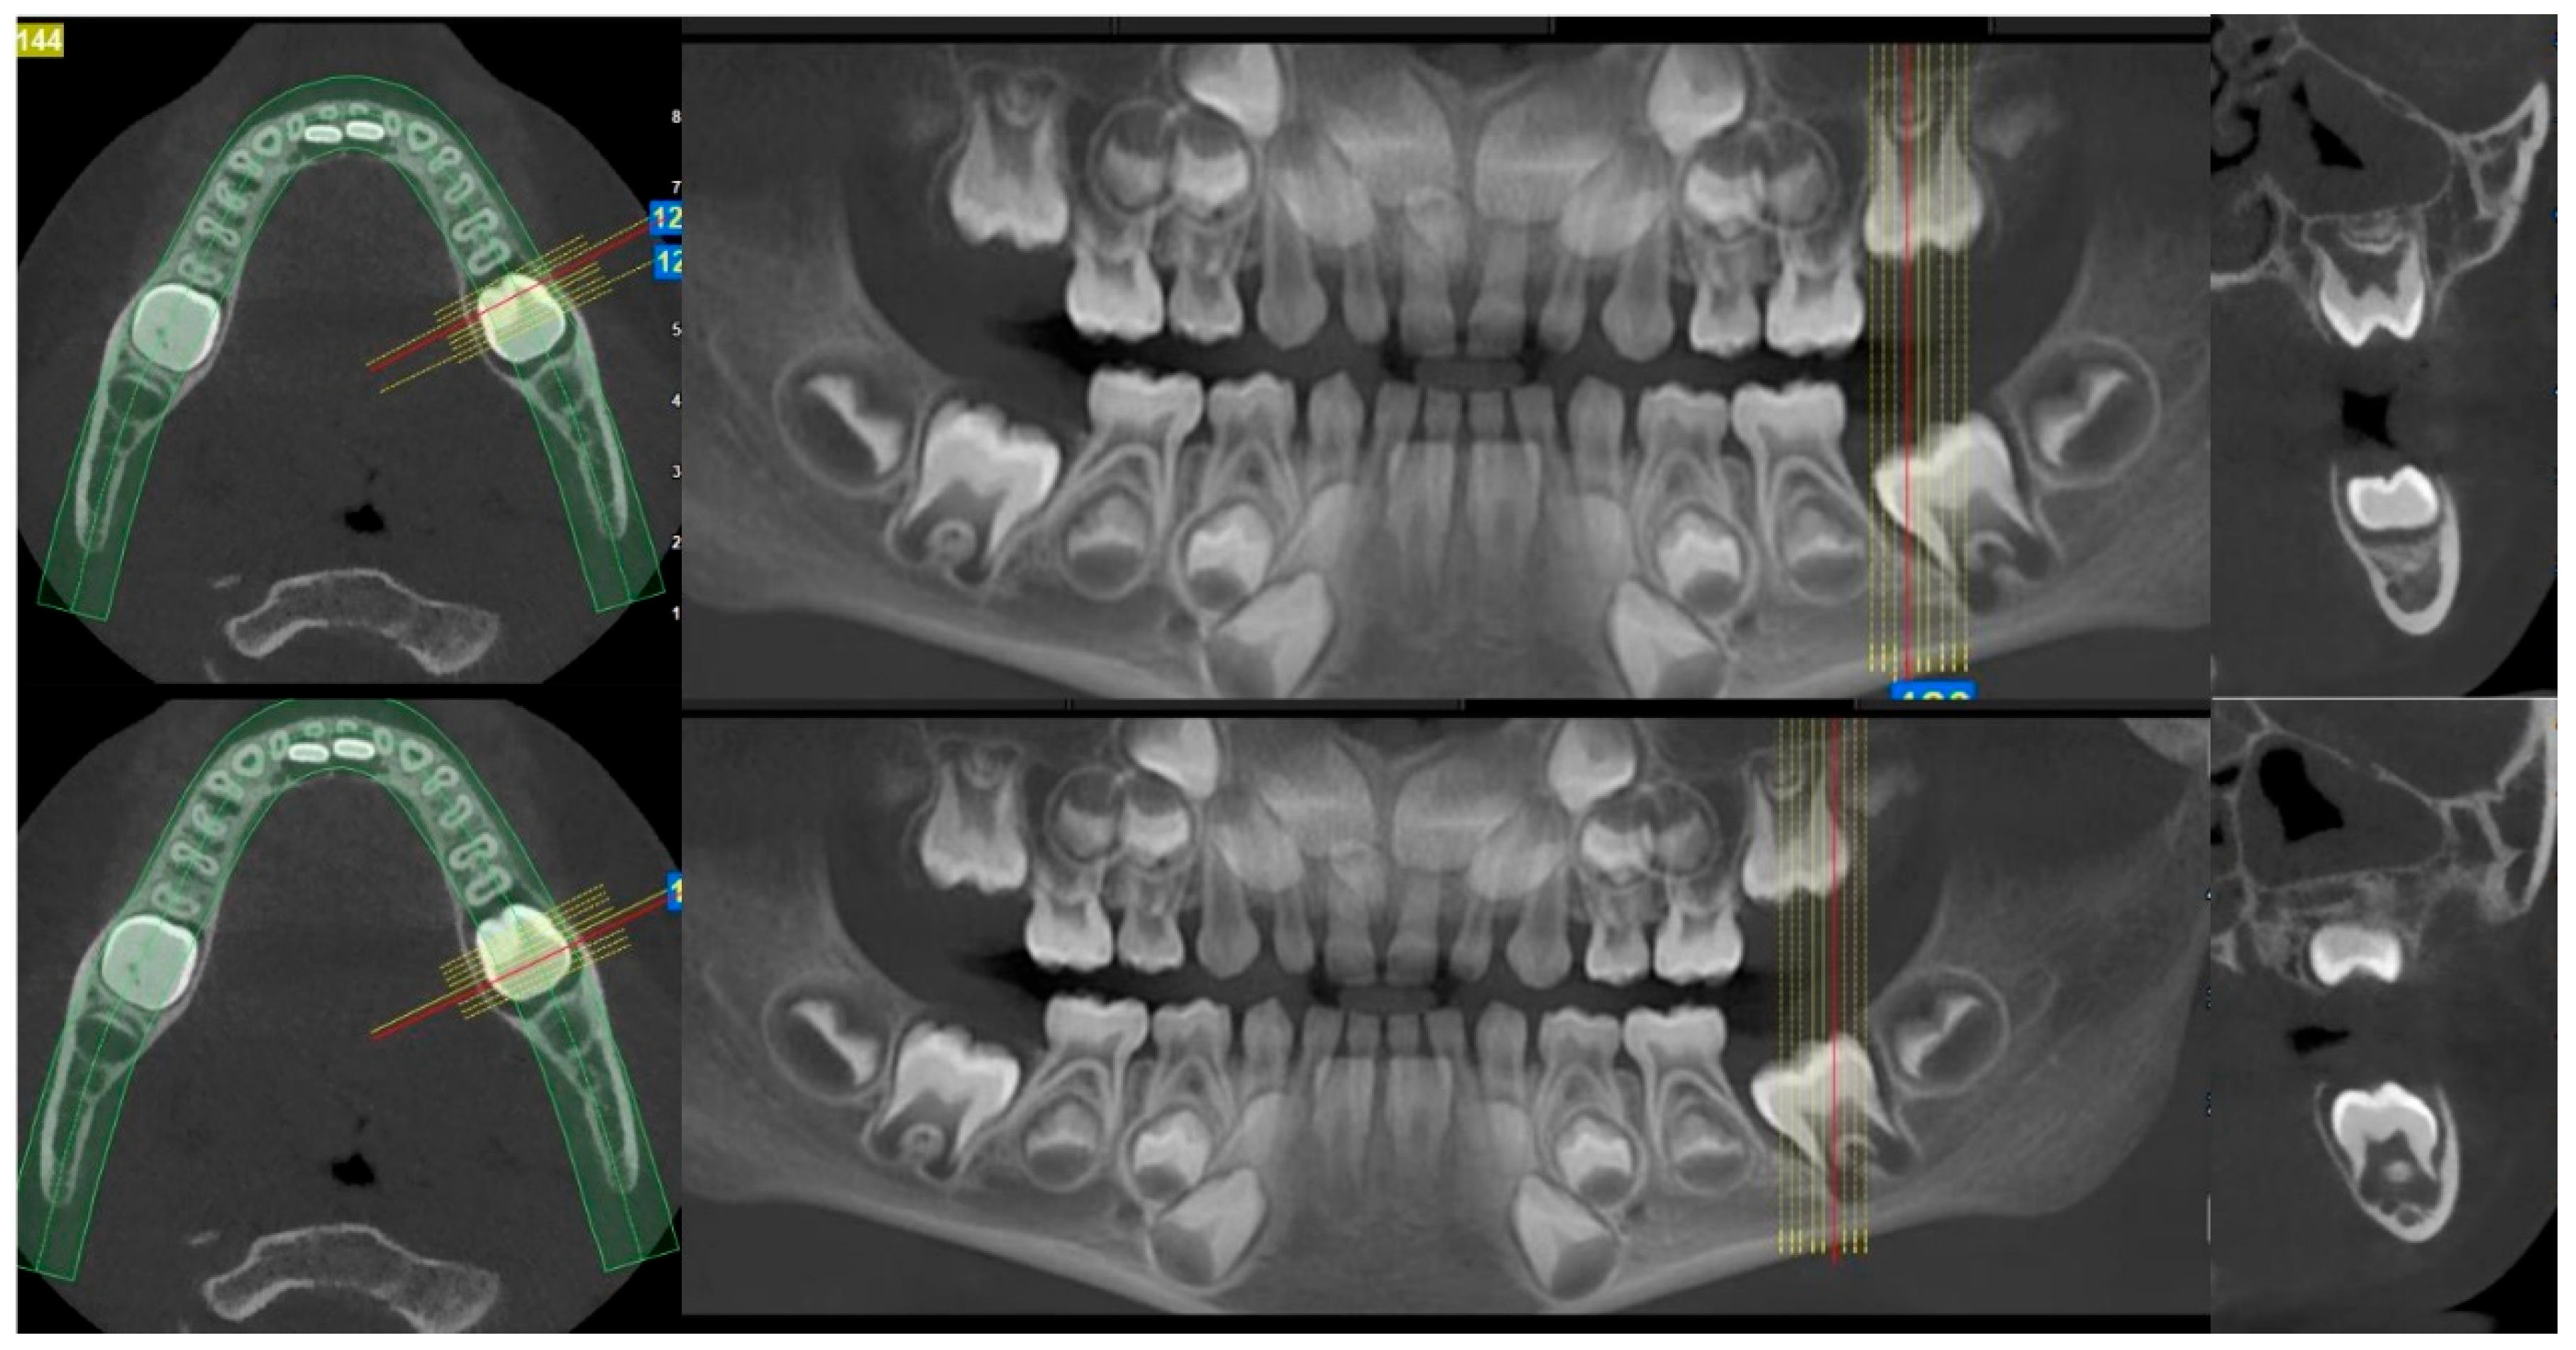

2. Case Presentation